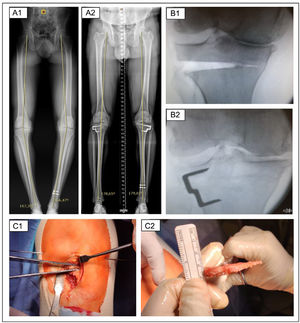

Partial weight bearing and knee flexion–extension are allowed from the first postoperative day. The full load is introduced progressively from the third week. They are visited in the first, second and third week to carry out a clinical control and ensure the correct evolution of the surgical wound. Subsequently, they are visited at 3, 6, 12 and 24 months to perform a clinical and radiological control (Fig. 2).

Radiological and intraoperative images of a patient undergoing two-stage bilateral CW-HTO. (A) Telemetry and HKA measurement pre (A.1) and postoperative (A.2). (B) Intraoperative fluoroscopy after removing the subtraction wedge (B.1) and after placing the fixation clip (B.2). (C) Intraoperative clinical images showing the execution of the bone cuts (C.1) and the verification of the thickness of the subtraction wedge once it has been removed (C.2).